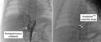

A 20-year-old primigravida was referred to the fetal cardiology clinic at 22 weeks’ gestation due to an intrapulmonary mass suggestive of pulmonary sequestration. The fetal echocardiogram showed a structurally normal heart and a tortuous feeding vessel arising from the abdominal aorta, proximally to the celiac trunk (Figure 1). She maintained regular follow-up, during which time the intrapulmonary mass gradually decreased in size and the collateral artery disappeared.